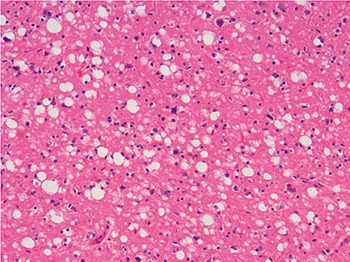

(A) A sheep with scrapie. An intense itching sensation (pruritus) is one of the symptoms of the disease. This causes the animal to engage in rubbing, scraping, or chewing behaviour, with resulting deterioration of the fleece. © Crown copyright 2011. Published with the permission of the Controller of Her Majesty’s Stationery Office. The views expressed are those of the author and do not necessarily reflect those of Her Majesty’s Stationery Office or the Veterinary Laboratories Agency or any other government department. Lesions in the grey matter of the brain of a sheep with scrapie:

(B) typical spongiform change in neurons (haematoxylin and eosin stain);

(C) spongiform change and astrocytic hypertrophy and hyperplasia (glial fibrillar acid protein stain). Magnification ×500

Figure 10 Sheep and brain section.